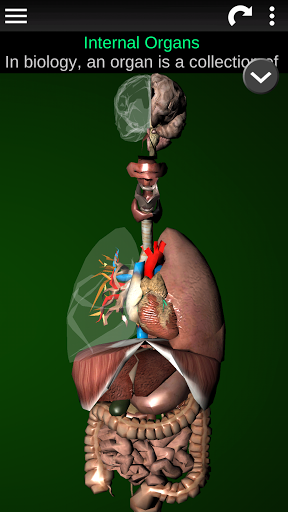

Internal Organs in 3D Anatomy لـ Vodafone Smart N9 Lite

(الأجهزة الداخلية في)

Internal Organs 3D Anatomy 3.1

يمكنك هنا تنزيل ملف حزمة تطبيق أندرويد "Internal Organs 3D Anatomy" الخاصة بجهازVodafone Smart N9 Lite مجانًا، نسخة ملف حزمة تطبيق أندرويد - 3.4 للتحميل على Vodafone Smart N9 Lite اضغط ببساطة على هذا الزر. إنه سهل وآمن. نحن نقدم فقط ملفات حزمة تطبيق أندرويد الأصلية. إذا انتهكت أية مواد موجودة في الموقع حقوقك قم بإبلاغنا من خلال